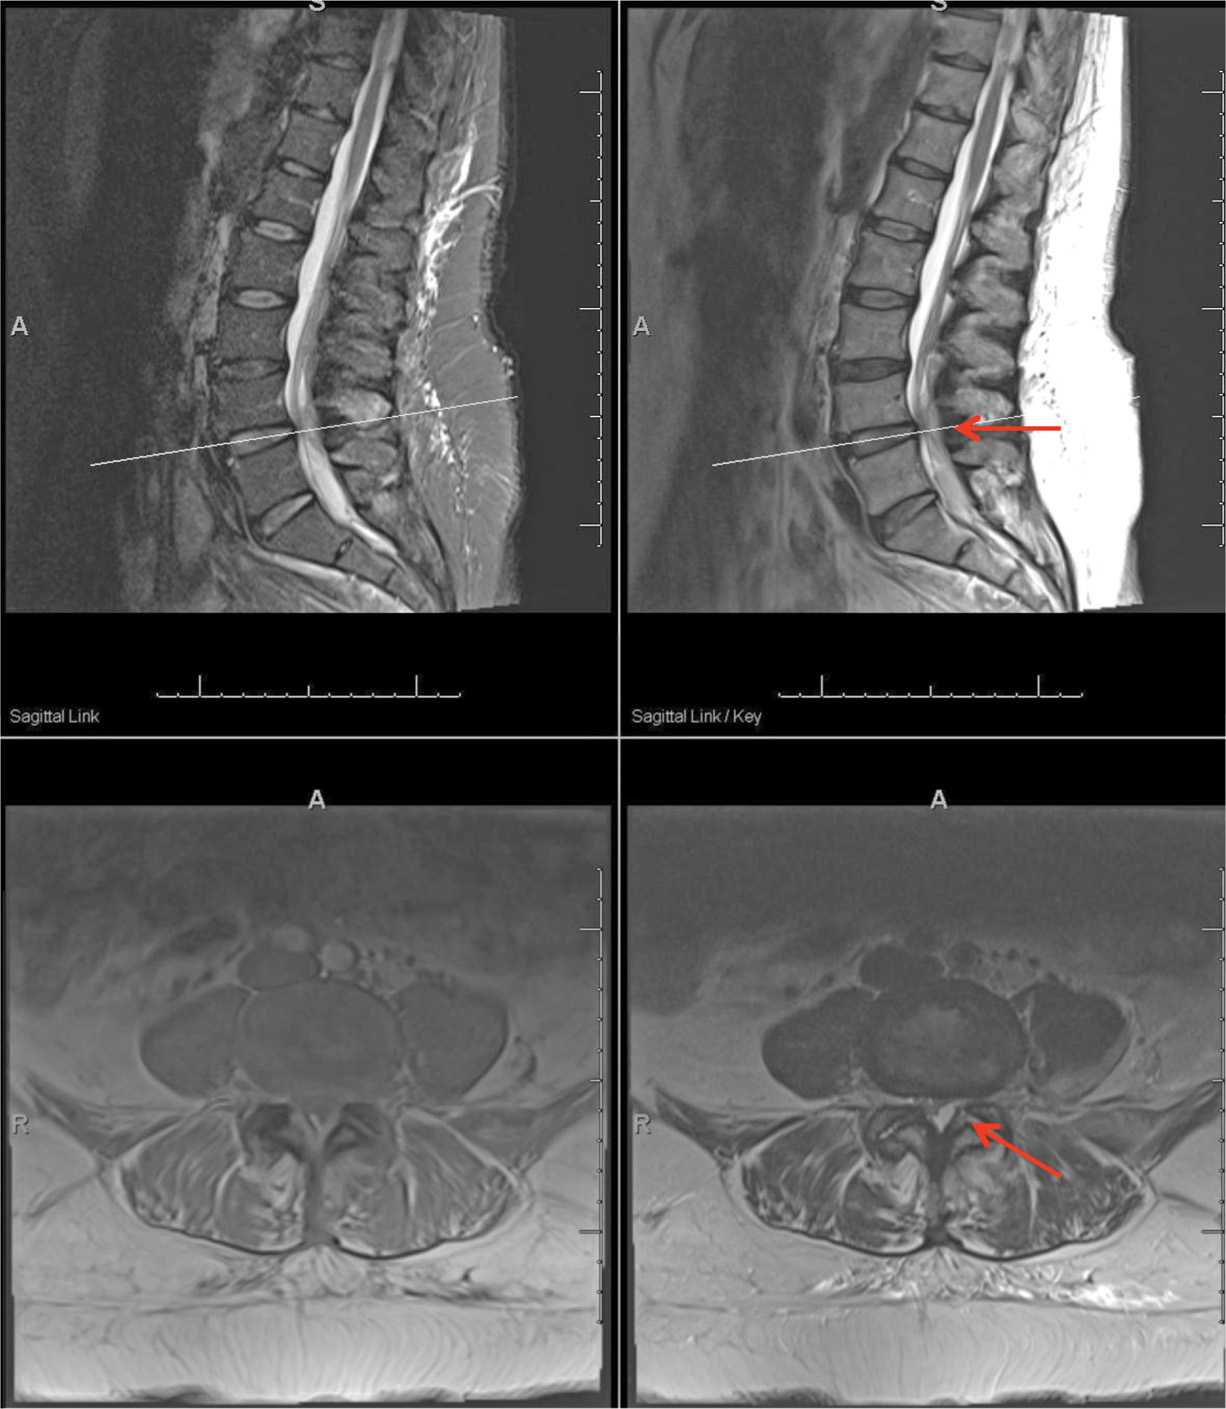

Representative resonance image showing facet effusion (arrows Facet Joint Effusion Symptoms The source of pain must be confirmed by clinical examination. The pain from an arthritic facet joint is often felt in the spine near the joint, but it can also refer to other locations. Depending on the number of facets affected, the severity of the condition, and the possible involvement of a nearby nerve root, one or more of the. Facet Joint Effusion Symptoms.

Lumbar Facet Joint Fluid A Reliable Sign of Lumbar Instability Cureus Facet Joint Effusion Symptoms Facet arthropathy can cause lower back pain and usually affects a specific part of your spine. The pain from an arthritic facet joint is often felt in the spine near the joint, but it can also refer to other locations. Facet joint syndrome can cause chronic pain in any region of your spine—from your neck to your low back. Poor. Facet Joint Effusion Symptoms.